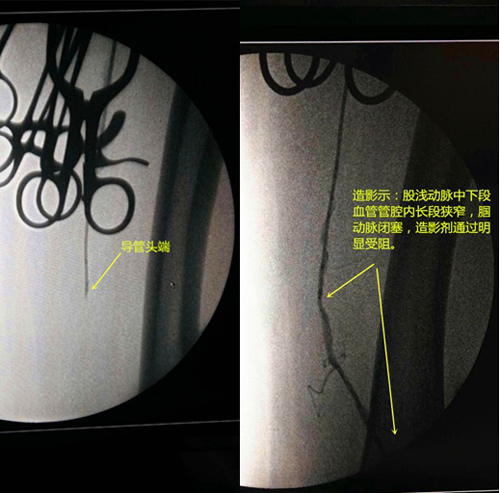

近期,我院放射科在老年综合科及手术室的密切协作下成功开展了“股动脉切开取栓术+股浅—腘动脉球囊扩张+支架植入术+胫前动脉、胫后动脉及腓动脉球囊扩张术”。手术在放射科介入手术室完成;术后在老年综合科赵宗国主任和邓鹏斌医师的精心治疗下最终患肢治愈。此例手术的成功开展关键在于临床能迅速诊断、外周介入能迅速手术及术后能精准治疗的多学科协作的成功案例;同时也填补了我院外周血管腔内成形术的空白,将最大程度的降低我院急性肢体动脉栓塞的截肢率、病死率。

患者入院后,及时开通绿色通道,老年综合科赵宗国主任与邓鹏斌医师积极联系放射科唐小平主任。经两科仔细讨论病情后决定即刻行左侧股动脉切开取栓术。赵主任反复与家属沟通后,在兰大一院介入科专家指导下当晚急诊行“股动脉切开取栓术+股浅—腘动脉球囊扩张+支架植入术+胫前动脉、胫后动脉及腓动脉球囊扩张术”。术中取出最长血栓为11cm(见下图)。